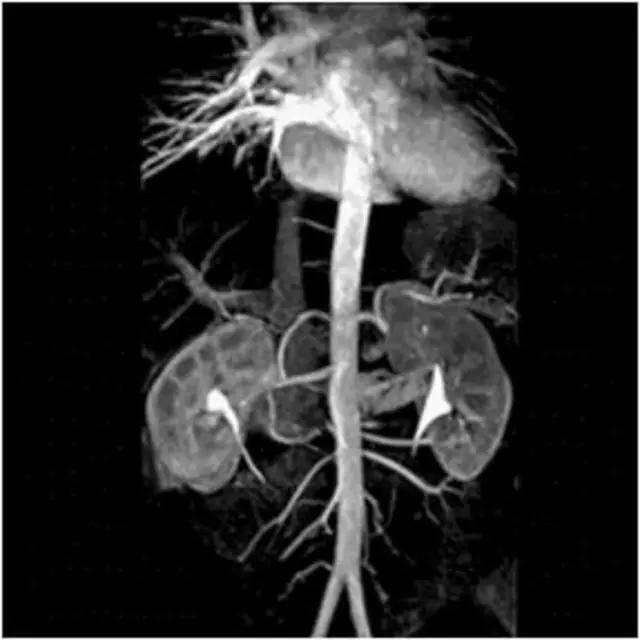

MRI最适宜的检查部位——

3、心脏大血管

流动(空白)效应:流动液体(血液、脑脊液)不产生信号。